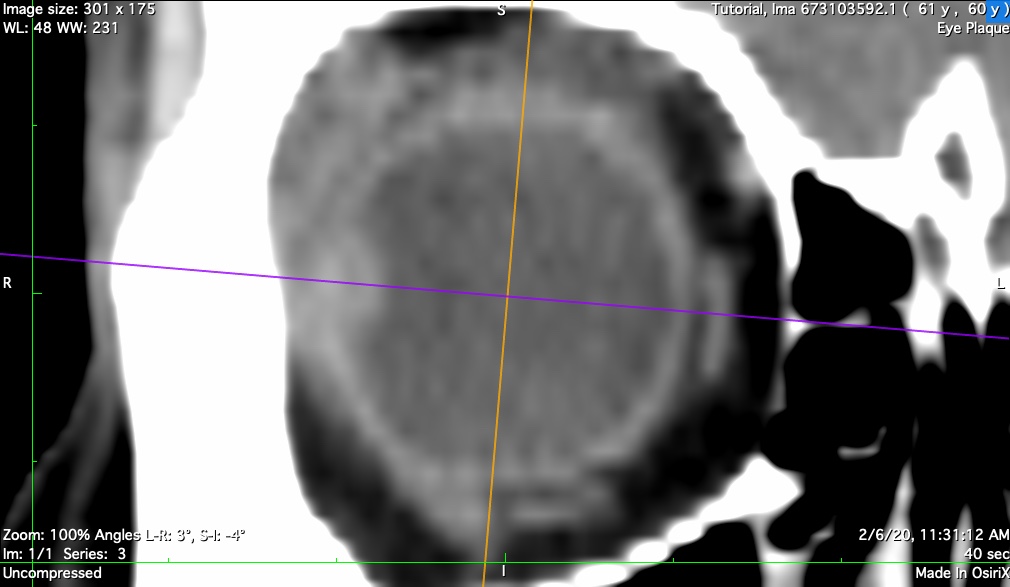

CT (or MR) Imaging

An orbital CT series, using a CT technique optimized for contrast of soft tissues (ie DO NOT use a bone imaging technique) with slice thickness <= 1 mm is the best option to model the eye for posterior and equatorially located tumors. MRI provides an acceptable alternative for ciliary and iris tumors when thin slices are available.

The orbital CT (or MRI) series is used to create these seven reconstructions that are used to build the 3D model of the eye. That 3D model is used to calibrate the fundus image, measure the optic nerve sheath diameter, and determine suture eyelet coordinates on the eye. If the tumor happens to be large enough to be visible in these reconstructions, the CT also provides confirmation of tumor location, shape and elevation as determined from the fundus and ultrasound imaging.

t-coronal

Coronal reconstruction through the tumor apex.